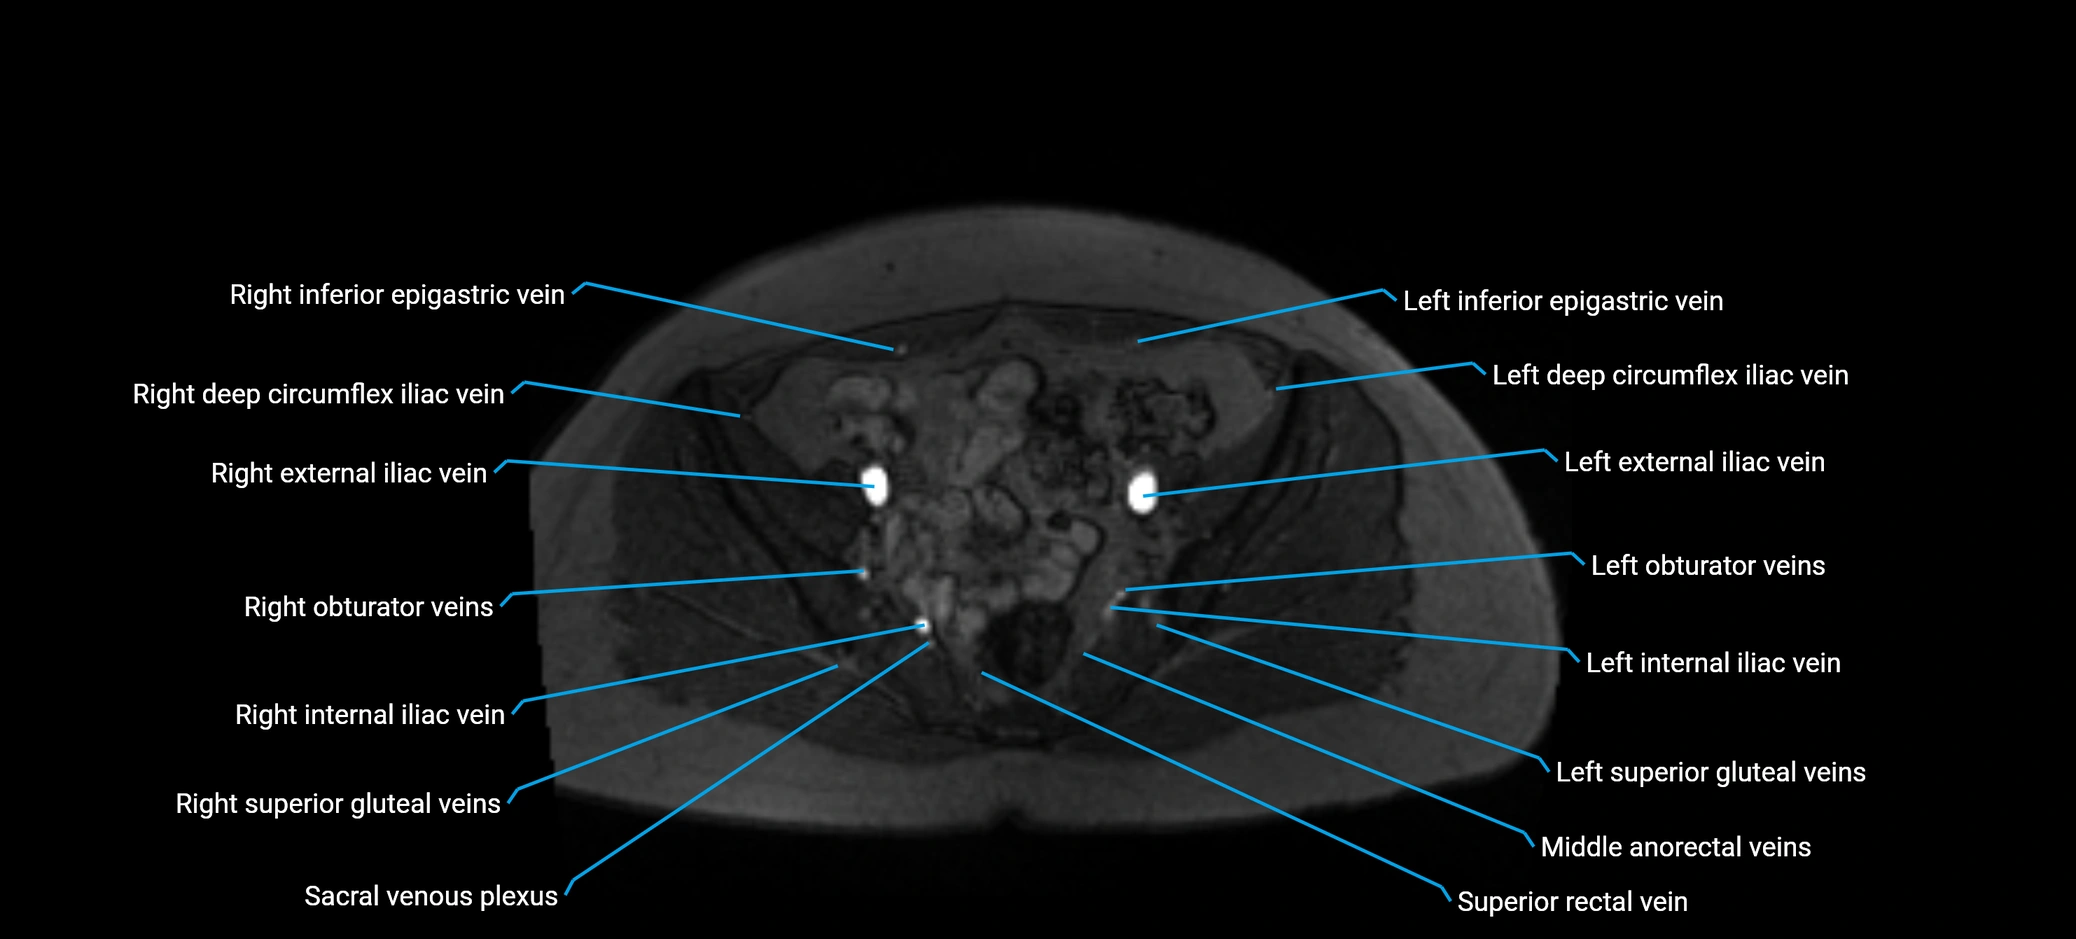

MRI image

image